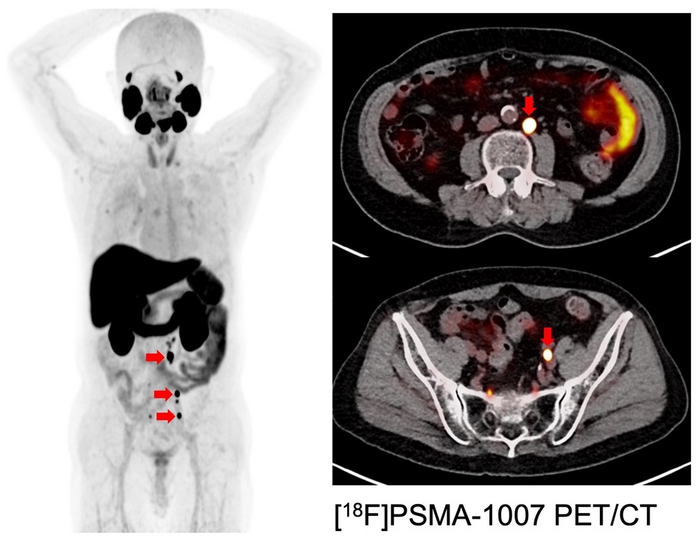

To develop a better option, the researchers investigated the effectiveness of another radioisotope called astatine ([ 211 At]) which is easy to manufacture with an accelerator using abundant materials. They implanted human prostate cancer cells in mice and treated them with a compound called [ 211 At]PSMA5. “The results were very impressive,” states collaborative researcher Frederik L.Giesel. “[ 211 At]PSMA5 accumulated at high levels in the tumor tissue and rapidly reduced tumor size.”

Importantly, [ 211 At]PSMA5 did not appear to have significant side effects in any major organs. Given its effectiveness in shrinking prostate tumors in mice, the researchers plan to launch an investigator-initiated clinical trial of [ 211 At]PSMA5 treatment for refractory prostate cancer in 2 years with the support of a translational research grant from the Japan Agency for Medical Research and Development.